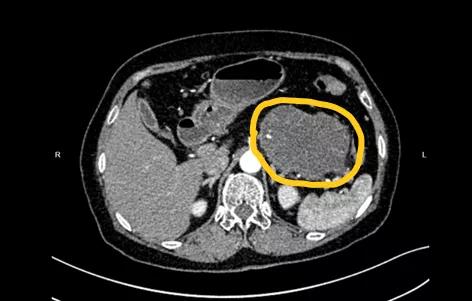

1月前,张阿姨出现了“肚子痛,胃口差”的症状,去了当地医院检查,发现胰尾部巨大囊性肿瘤,有癌变可能。

曹教授仔细看过片子后告诉他们:“胰腺体尾部肿瘤比较大了,大概有拳头那么大。内部能够看到一些分隔和钙化,中间的胰管显示不清楚。初步考虑IPMN的可能性大。”

曹教授耐心解释道:“这是胰腺某种肿瘤性囊肿的简称,全名应该是胰腺导管内乳头状黏液瘤。您的肿瘤很大,从片子上看,也不排除伴有恶变的可能。”

第二天,张阿姨住进了邵逸夫医院,主管医师丁国平主任医师为张阿姨进行了详细的术前检查,仔细评估后,医生认为张阿姨虽然肿瘤较大,幸运的是并未侵犯腹腔干等重要血管,还可以在腹腔镜下微创切除。

曹教授告诉张阿姨,根据手术后的切片病理报告,她得的是一种叫导管内乳头状黏液性肿瘤的胰腺囊肿性疾病,目前确实已经有局部癌变了。但幸运的是癌变还是早期的,T1期,也没有淋巴结的转移,下一步建议在肿瘤内科密切随访观察和治疗。